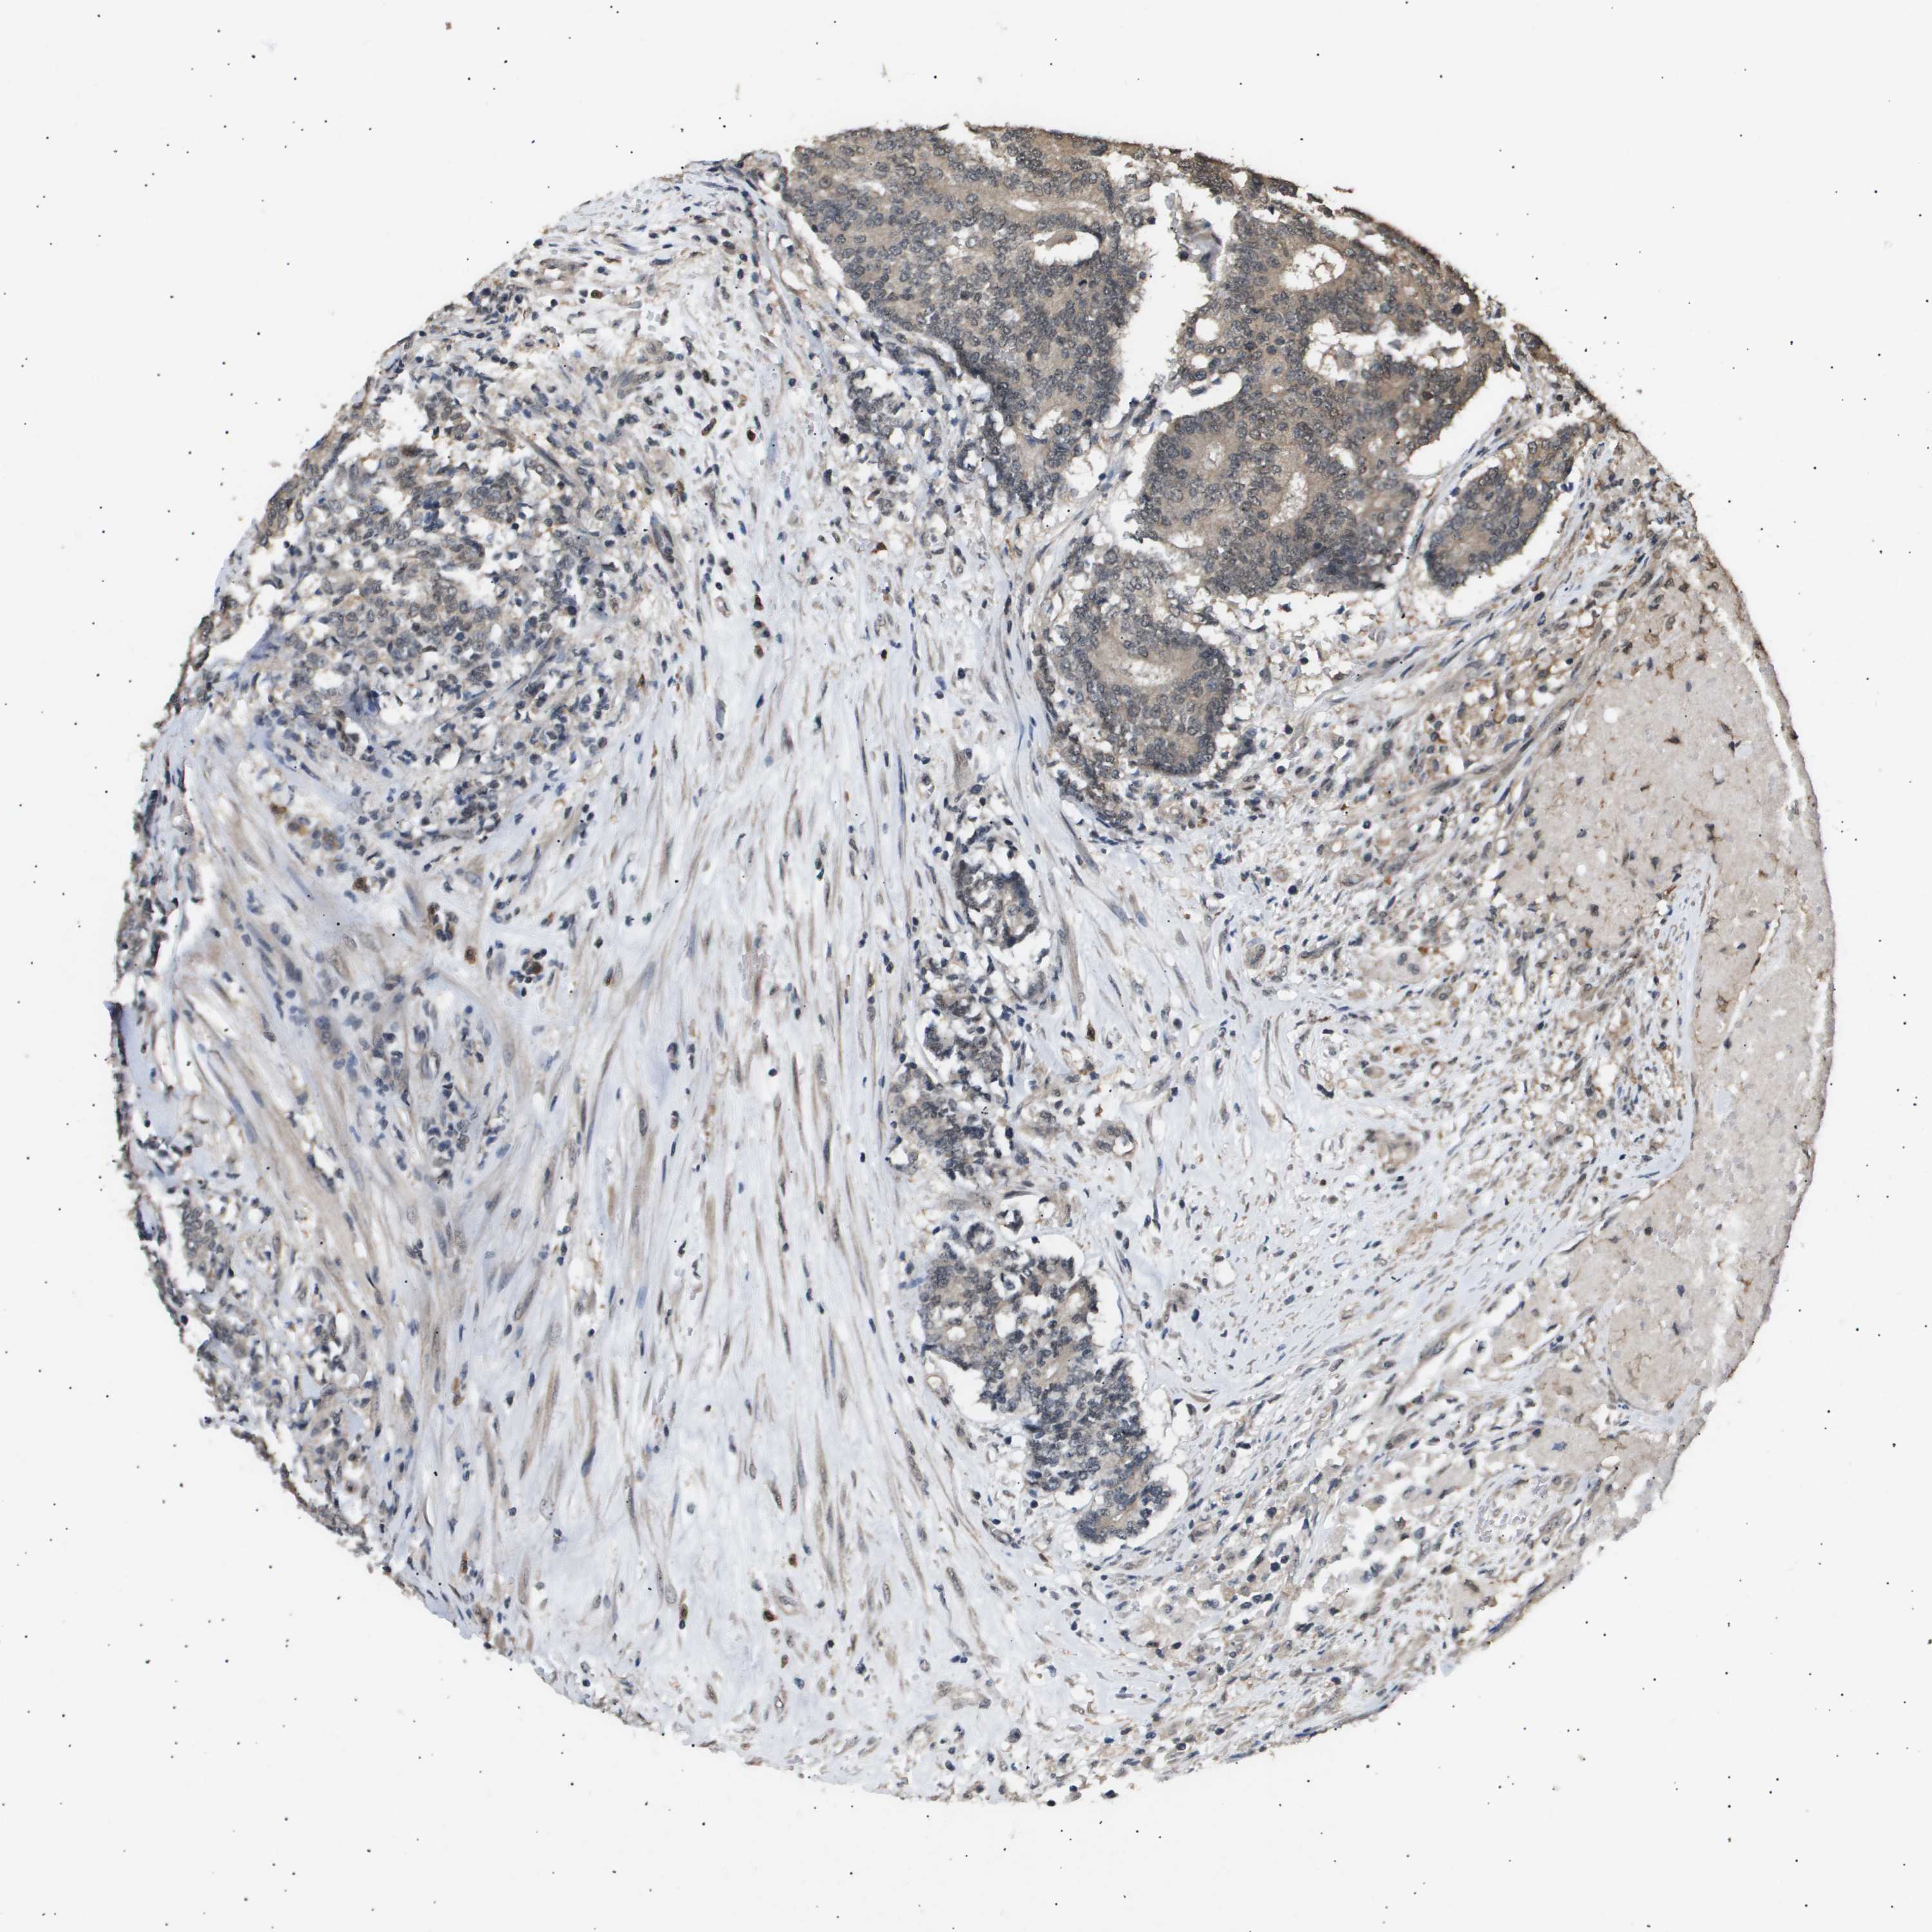

PROSTATE CANCER - Protein expressioni

A mouse-over function shows sample information and annotation data. Click on an image to view it in a full screen mode. Samples can be filtered based on level of antibody staining by selecting one or several of the following categories: high, medium, low and not detected. The assay and annotation is described here.

Antibody stainingi

Antibody staining in the annotated cell types in the current human tissue is reported as not detected, low, medium, or high, based on conventional immunohistochemistry profiling in selected tissues. This score is based on the combination of the staining intensity and fraction of stained cells.

Each image is clickable and will lead to virtual microscopy that enables deeper exploration of all samples and also displays staining intensity scores, fraction scores and subcellular localization as well as patient and tissue information for each sample.

Antibody CAB016136

Antibody CAB017773

Staining

High

Medium

Low

Not detected

Intensity

Strong

Moderate

Weak

Negative

Quantity

>75%

75%-25%

<25%

None

Location

Nuclear

Cytoplasmic/membranous

Cytoplasmic/membranous,nuclear

Adenocarcinoma, Low grade

Adenocarcinoma, High grade